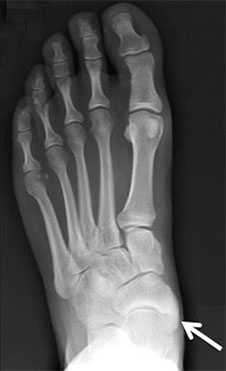

Добавочная ладьевидная кость классифицируется в соответствии с рентгенологическими ее особенностями:

- Сесамовидная косточка в толще сухожилия задней большеберцовой мышцы в области его прикрепления к ладьевидной кости

- Добавочная ладьевидная кость, сочленяющаяся синхондрозом с ладьевидной костью

- Костный выступ ладьевидной кости

Рентгенограмма стопы при 1 типе добавочной ладьевидной кости

Рентгенограммы стоп: 3 тип добавочной ладьевидной кости